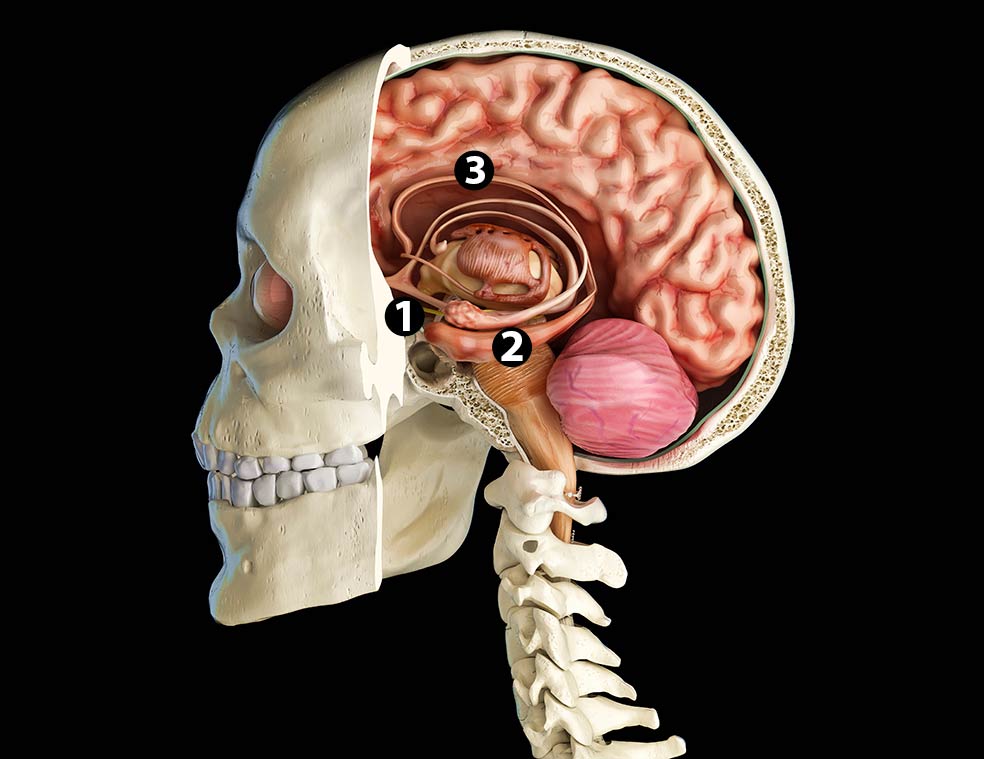

Más que zonas corporales concretas, Francisco Mora –catedrático de Fisiología Humana y autor de Cómo funciona el cerebro (Alianza Editorial)– cree que son cruciales «las interconexiones de las redes neuronales con distintas partes del cerebro». Sobre todo cuando se producen en áreas como el hipocampo, el núcleo accumbens o el giro cingular, que forman parte del sistema límbico del cerebro, involucrado en nuestra vida afectiva y en nuestras emociones.

¿Por qué enchufaron los electrodos en el giro cingular? «Porque tiene muchas conexiones con regiones cerebrales que coordinan respuestas complejas. El haz del cíngulo es una encrucijada para la materia blanca, así que puede afectar a redes extensas en todo el cerebro», responde el profesor Willie. La felicidad tiene su parte química. «Es un proceso neuroquímico que consiste en la liberación de dopamina en el sistema límbico». Es la definición que hace Eduardo Calixto, jefe de Neurobiología del Instituto Nacional de Psiquiatría de México. El giro cingular, una estructura del sistema límbico, quizá sea el guardián de la llave de la felicidad.

El mapa del placer en el cerebro